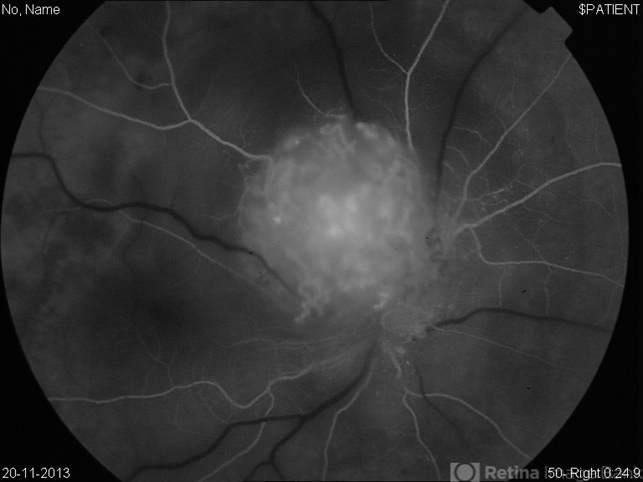

- Early FA of optic disc capillary hemangioblastoma

- FA showed early hyperfluorescent spots over the mass.